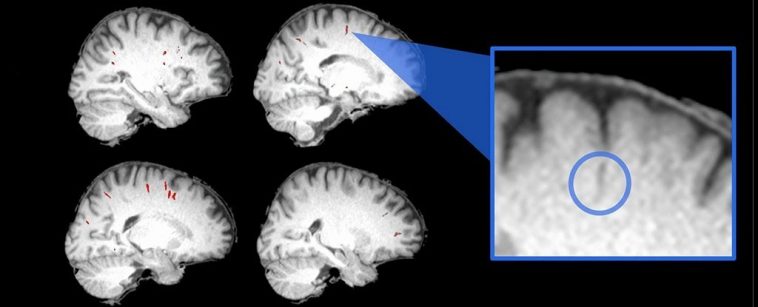

Researchers from across the US compared a series of magnetic resonance image (MRI) scans of 15 astronaut brains taken prior to a six-month stay on the International Space Station, and up to six months after their return.

Using algorithms to carefully assess the sizes of perivascular spaces (gaps in brain tissue thought to facilitate the balance of fluids), the team found time spent in orbit had a profound effect on the brain’s plumbing. For the first-timers, at least.